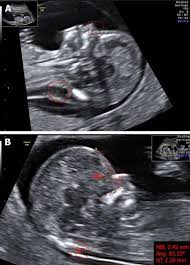

Down Syndrome can include cardiovascular central. A review on the various soft markers identified for the detection of down syndrome from the first and second trimester ultrasound fetal images has been made. In this low risk population soft markers were found in 59 of fetuses at second trimester ultrasound.

There are specific characteristics identified during an ultrasound exam in the second trimester of a womans pregnancy that are possible indicators for Downs syndrome. Both major structural abnormalities and minor soft markers can be detected by ultrasound in fetuses affected with aneuploidies. There are many other prenatal screening tests available with better detection rates for Down syndrome than the mid-trimester ultrasound.

Markers were isolated in 51 multiple in 07 and combined with anomalies in 01 1. Most of the time this represents nothing but in some cases it may be caused by Down syndrome cytomegalovirus CMV. The following are ultrasound markers that are seen more frequently in fetuses with Down syndrome. The 1st 2nd trimesters can show anatomical signs frequently seen in fetuses with Down Syndrome or other genetic accidents that result in 3 copies of a specific chromosomeKnowing your risk of DS calculated by FUS findings gestational maternal age 1st 2nd trimester maternal blood screens a higher-resolution FUS helps you decide if you want. Most cases 95 had a single marker 4 had two markers and 1 had three or more markers when soft markers were first identified 10. They do not affect the function of the muscle or the beating of the heart. But there is nothing to worry about and my child is perfectly normal Becauese my first-trimester scan and blood test were both normalBUT I need to make an appointment with a genetic. Markers were isolated in 51 multiple in 07 and combined with anomalies in 01 1. And a day after my midwife called me and told me that they found two soft markers for down syndrome.